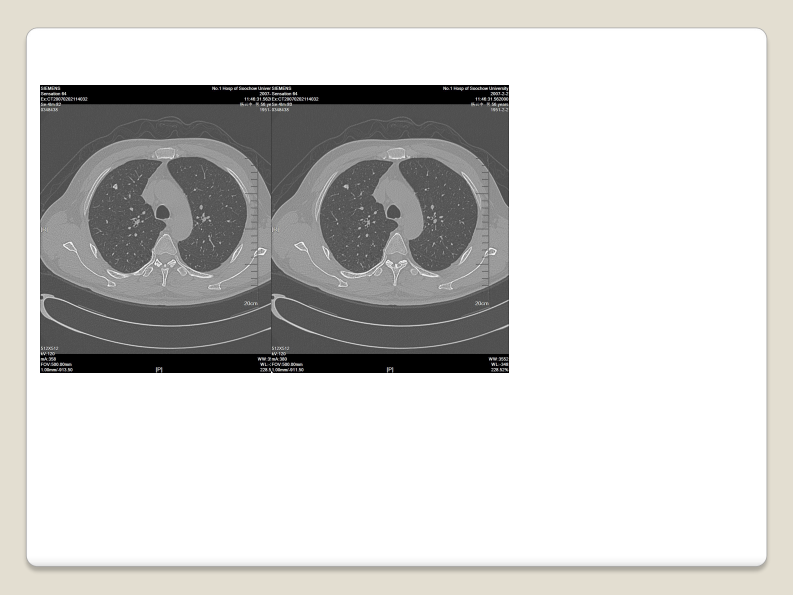

磨玻璃结节的影像分析--郭亮.pdf